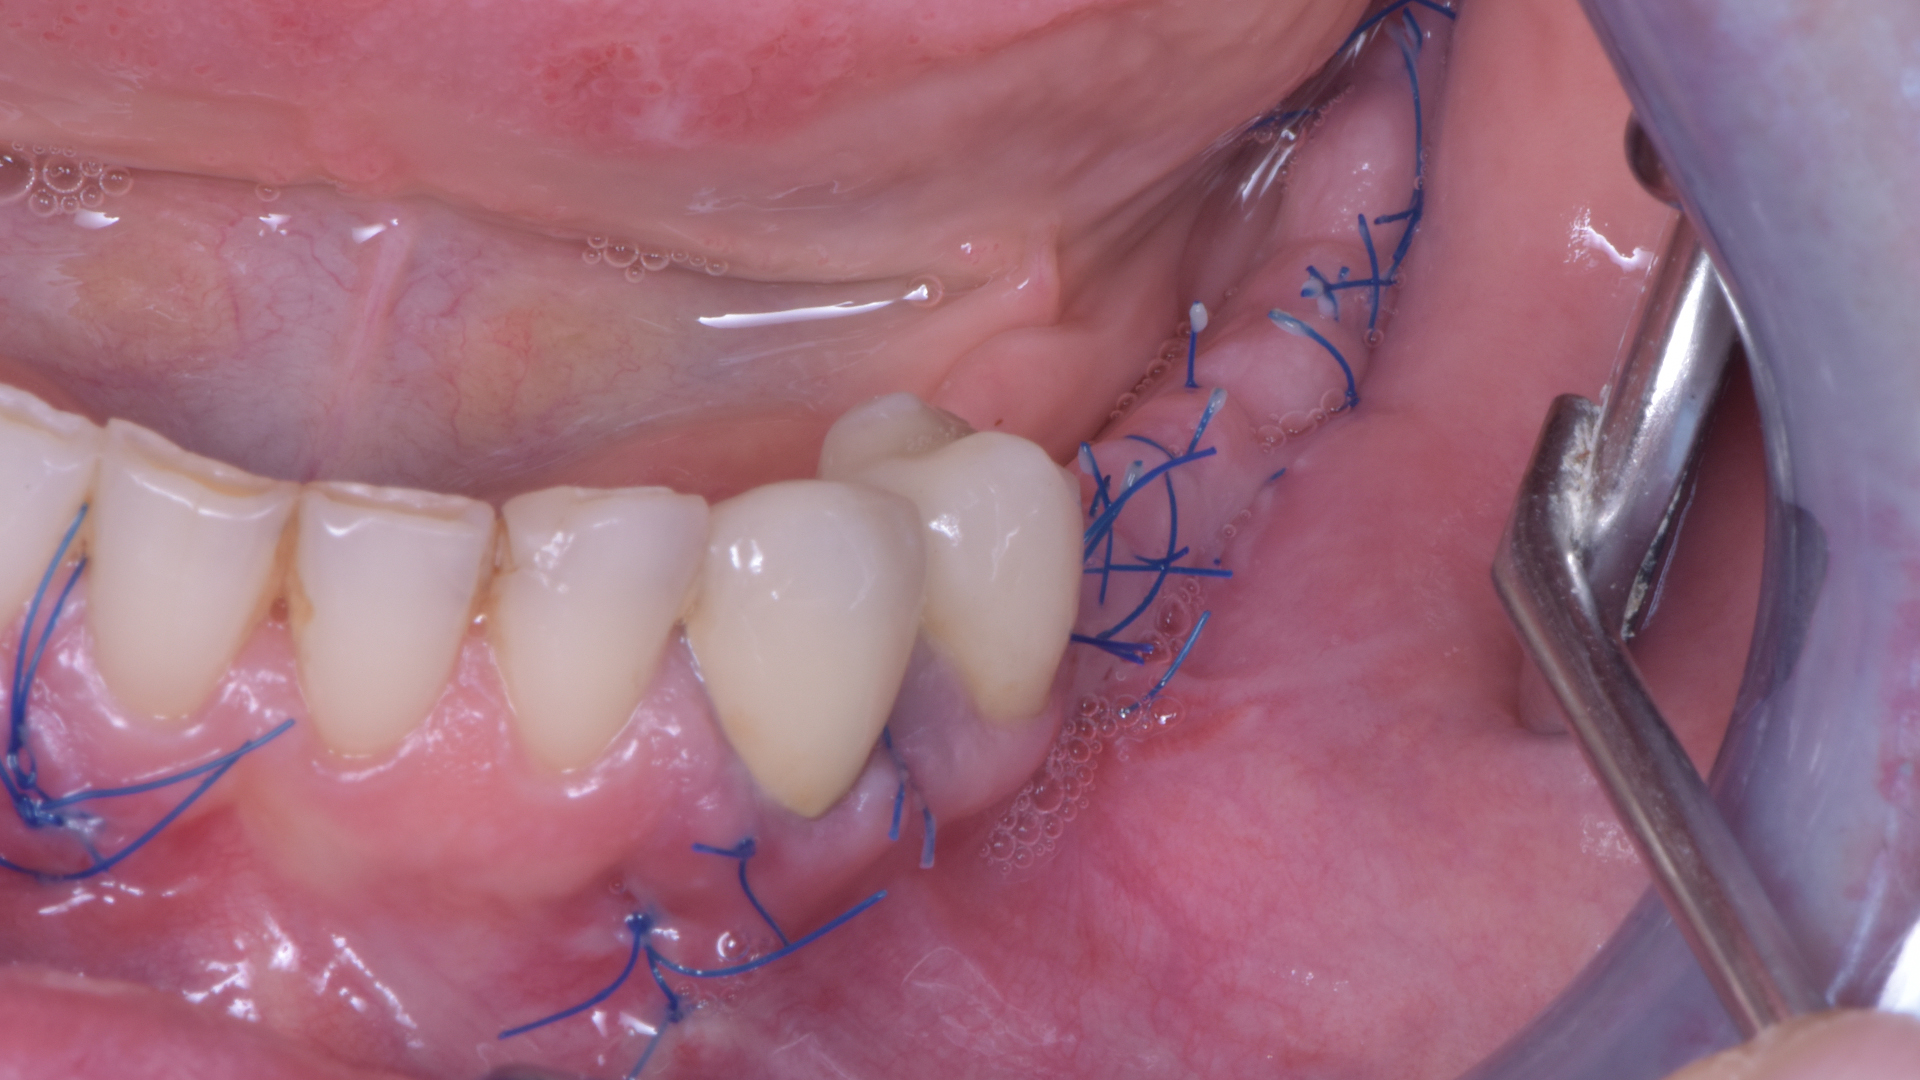

Se vuoi evitare latanto temuta ESPOSIZIONE non puoi suturare come cavolo ti pare. DEVI suturare così:

- Parti dallo scarico mesiale. Punti staccati, quello è facile.

- Sutura tutto il taglio con punti a materassaio orizzontale inserendo l’ago ad almeno 4 mm dal taglio.

- Chiudi poi i margini dei lembi con punti staccati tra un materassaio e l’altro.

Le guarigioni a quel punto saranno queste a 15 giorni. E’ difficile pensare che qui qualcosa possa esporsi… non credi??!!